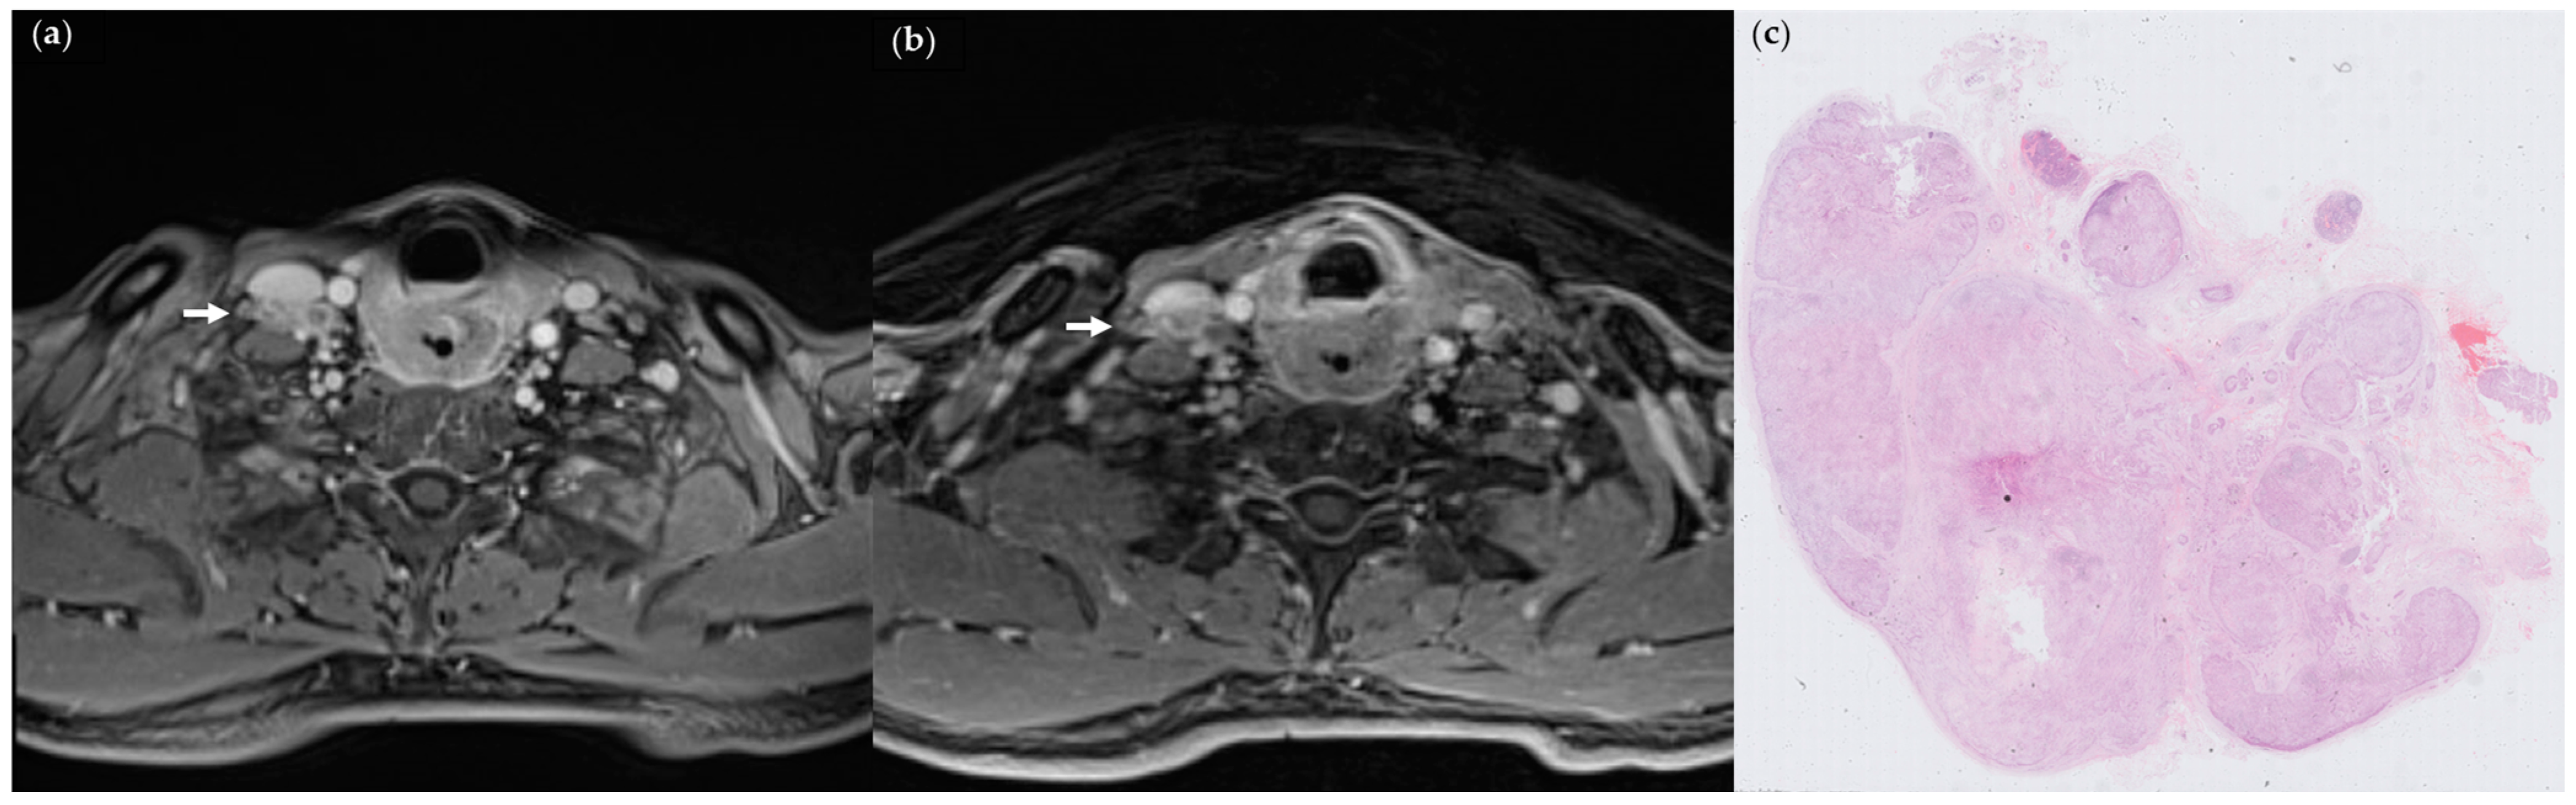

3.2. Comparison between StarVIBE and VIBE

3.3. Association of MR Features with Histologically Confirmed ENE